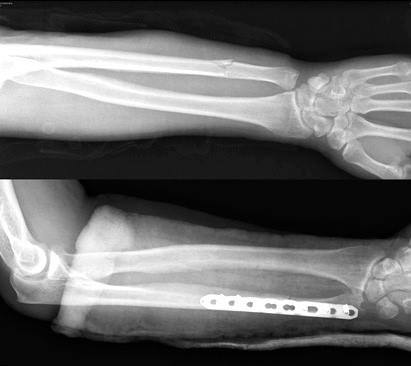

Чаще остальных фиксаторов, при переломах лучевой и локтевой кости используются пластины и специальные винты. Остеосинтез перелом лучевой и локтевой кости является «золотым стандартом» в травматологии.

Современные пластины и винты позволяют зафиксировать отломки в области перелома в правильном с анатомической точки зрения положении, а также стабильно удержать это положение до сращения перелома.

Сращение диафиза кости у взрослого занимает много времени. Через шесть недель на рентгене можно увидеть первые признаки костной мозоли. Через 10 недель прочность кости в области перелома достигает до 80 процентов от исходной. Полная консолидация и перестройка кости может занять до нескольких лет. После того как перелом сросся, можно задуматься о удалении металлофиксатора, хотя это и является необязательным. В некоторых случаях метталофиксатор может вызывать дискомфорт, ощущение болезненности. Обычно стержни и пластины из лучевой и локтевой кости удаляются не ранее чем через 2 года, при условии наличия рентгенологических признаков консолидации перелома.